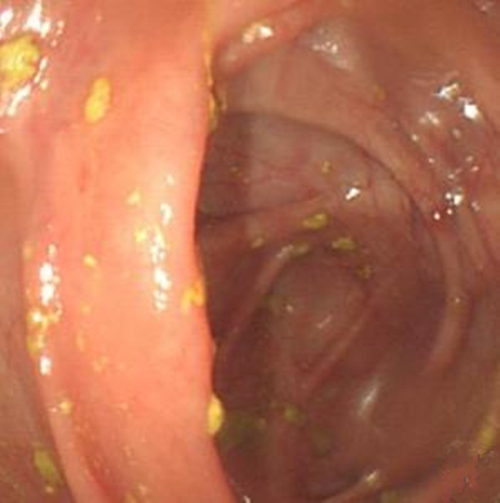

纖維結腸鏡檢查

慢性結腸炎圖片